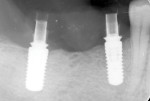

A 65-year-old woman with no contributory medical history was referred by her general dentist for the restoration of the mandibular right quadrant with an implant-supported fixed restoration. Using 3D planning and a surgical guide, implants Nos. 29 and 31 were placed. After a healing period of 8 weeks, as recommended by the manufacturer, the two implants were ready for restoration (Figure 1 and Figure 2).